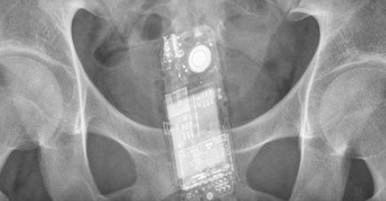

Un detenuto ha nascosto un cellulare nell’ano ed è stato scoperto dalla polizia penitenziaria mentre rientrava nel carcere di Aversa. Al momento della perquisizione, nell’orifizio anale dell’uomo è stato rinvenuto uno smartphone grazie all’ausilio del metal detector. Il carcerato, che ritornava nella struttura detentiva normanna, dopo un permesso premio concesso dall’autorità giudiziaria, sarà ora punito con una sanzione per violazione delle regole.